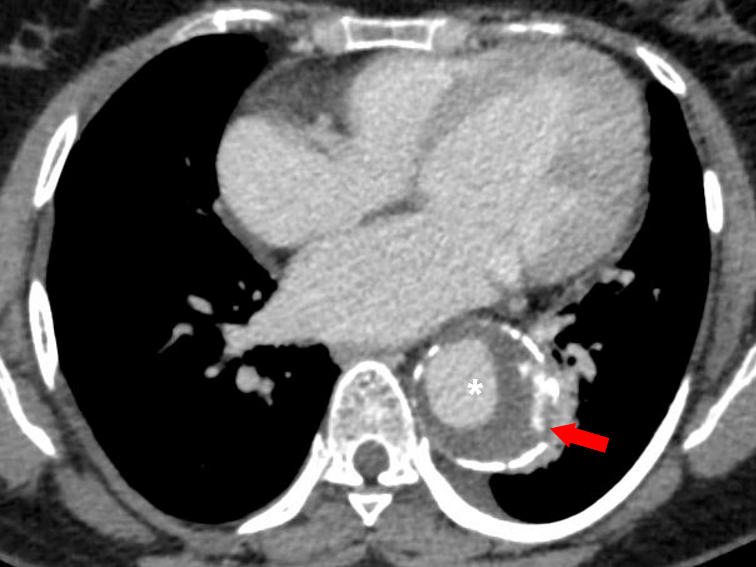

Figure 10 a-b Intramural hematoma. (a) Axial non-contrast CT thorax image in a case of thoracic aortic aneurysm (white asterisk) shows a crescentic thickening of high attenuation within the wall of the descending thoracic aorta (red arrow). Intimal calcifications are seen displaced inwards (yellow arrows). (b) A contrast-enhanced CT thorax image of the same patient shows no enhancement of the IMH. Bilateral pleural effusions are also seen in both images (a) & (b).